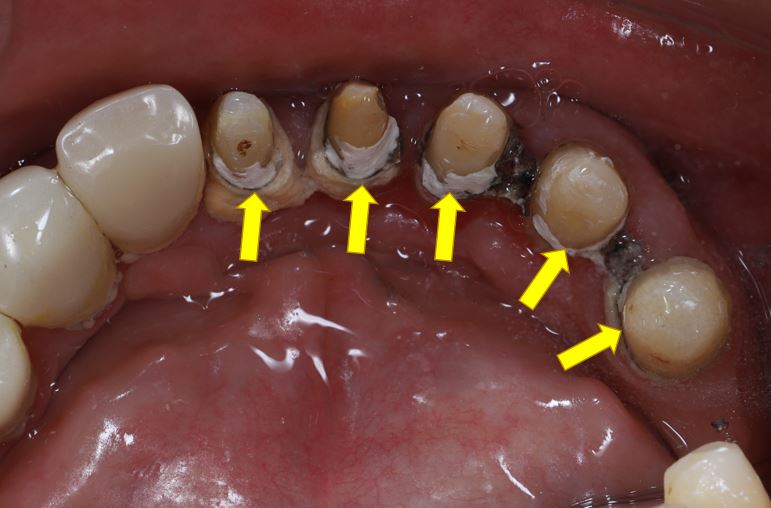

图4. 全冠边缘不密合的临床表现。牙齿不美观,且容易使脏东西堆积,导致牙齿进一步龋坏,以及牙龈发炎和退缩。这种有明显缺陷的全冠一般需要重新制作。

图7. 清洁不到位,牙龈退缩。拆除原来的牙冠,可以看到牙根上有大量的牙石。